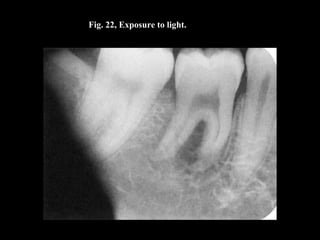

Fig. 22, Exposure to light.